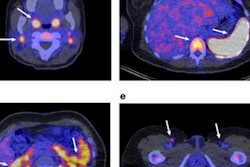

Comparatively, after five runs, their method produced consistent Zr-89 DFOSq-Durvalumab radiotracer yields of 75% and an automatic process time of 40 minutes, according to the findings. In addition, the group tested the radiotracer in mice, with Zr-89 DFOSq-Durvalumab showing excellent ability on PET imaging to detect cancer.

Further, the group noted they plan to employ the method in a large clinical trial using Zr-89 DFOSq-Durvalumab PET imaging before, during, and after patients undergo Durvalumab therapy to further characterize the drug's effects.